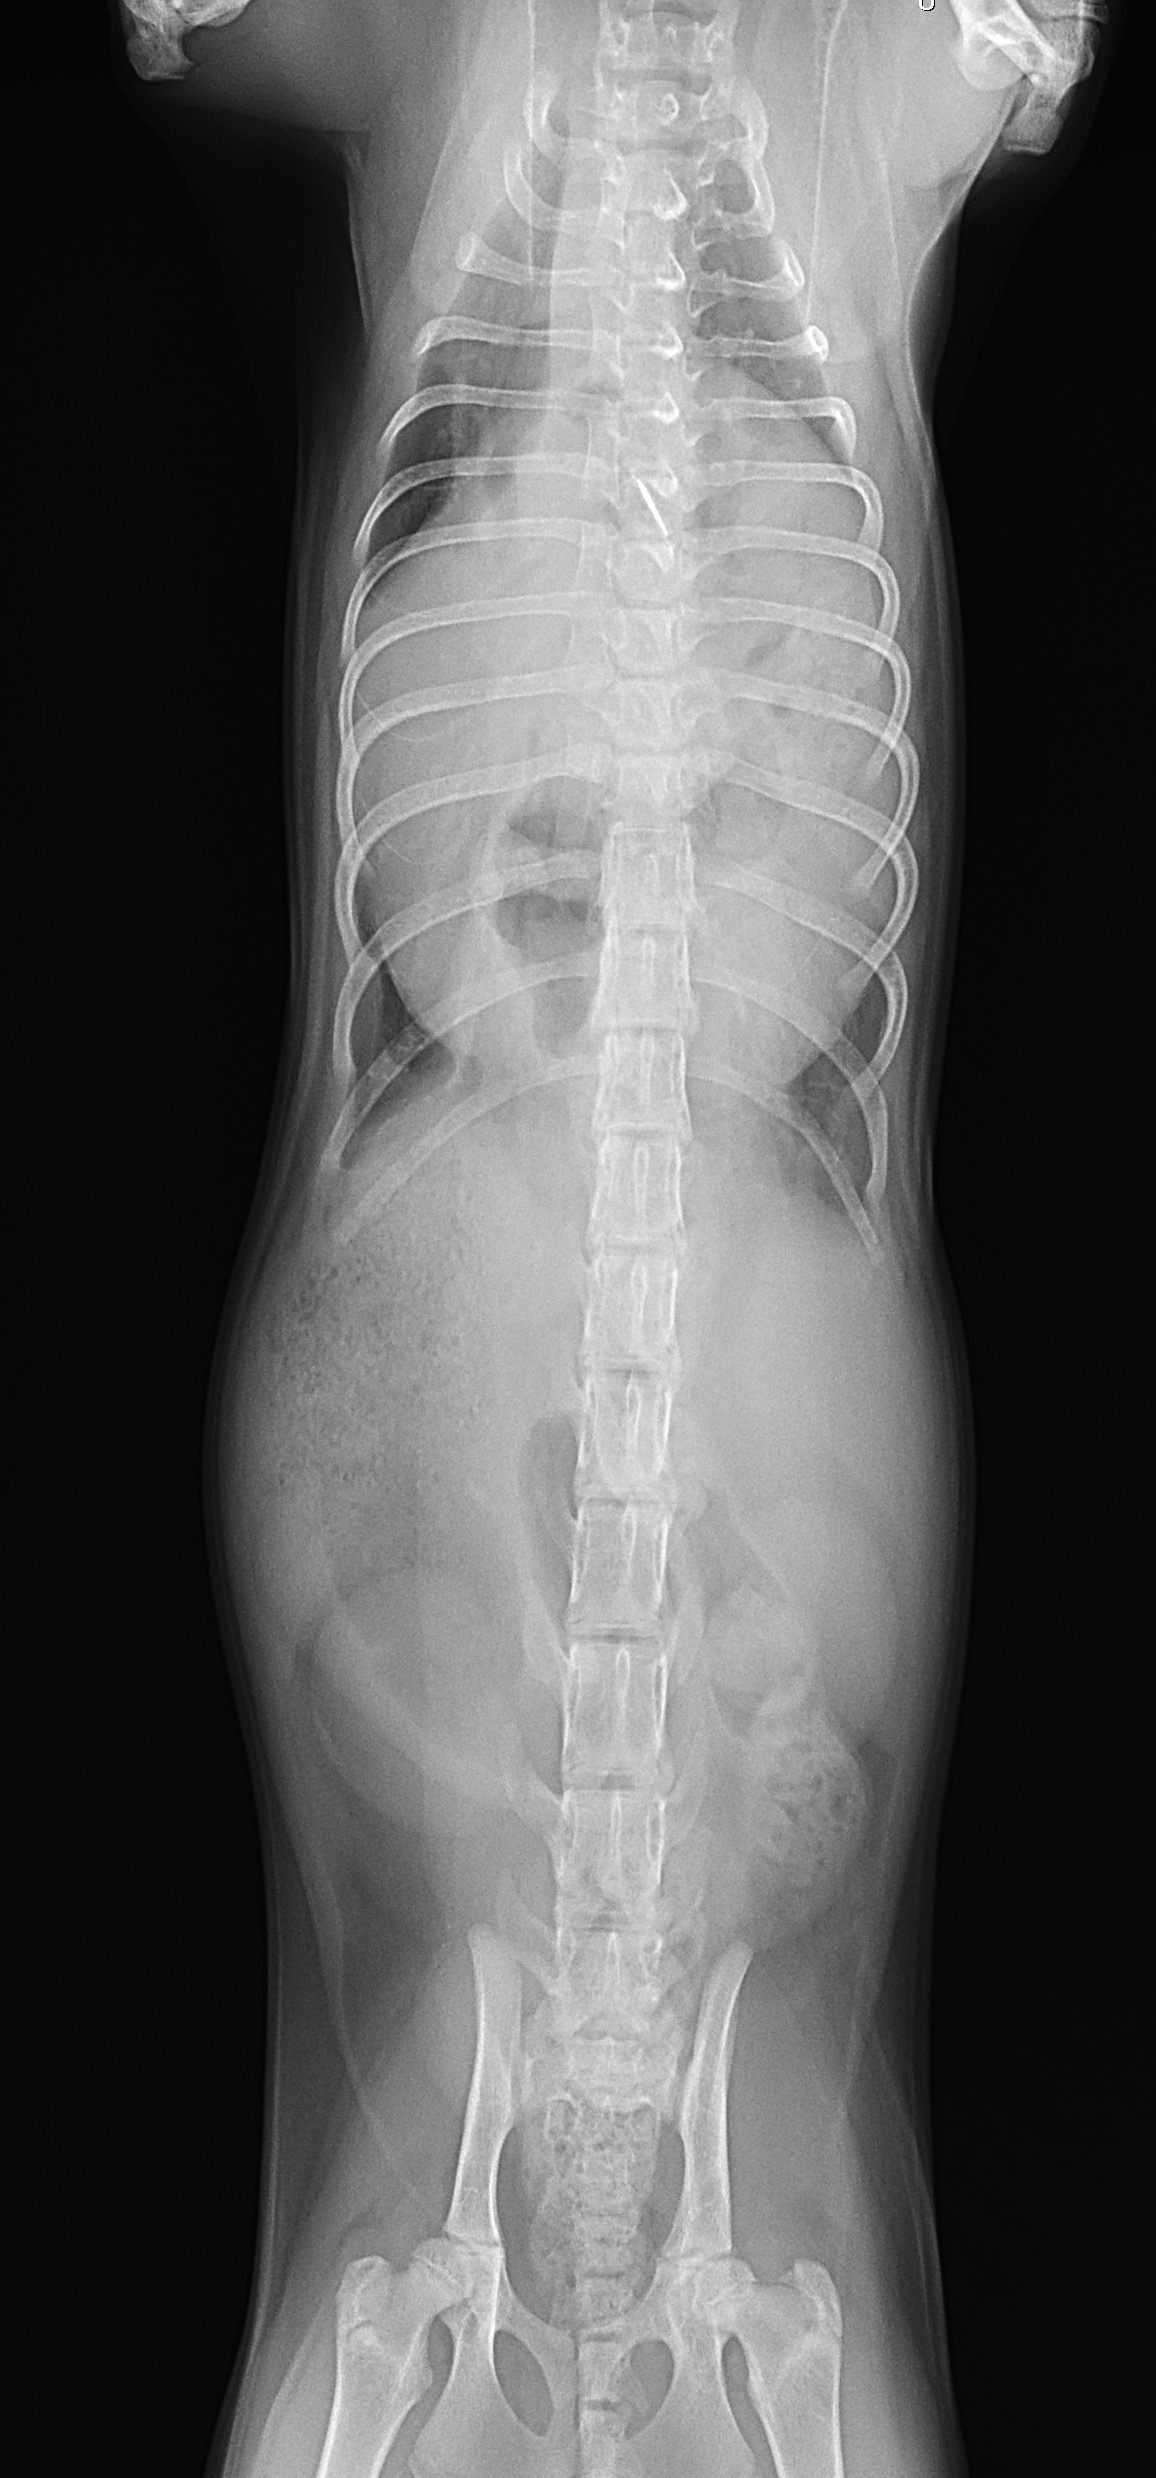

先天性心嚢横隔膜ヘルニア

若い猫が、普段はとても元気だけど、遊んだ後などに咳をする。呼吸が早くなる時がある。などの呼吸器症状で主治医を受診しました。エックス線検査の結果、心嚢横隔膜ヘルニアと診断されました。主治医より、外科的な対応のため紹介受診となりました。腹部正中切開の後、心嚢内に逸脱した、肝臓、胆嚢、小腸を腹腔内に戻し、横隔膜を再建しました。術後には、再拡張性肺水腫という病態が発生する可能性があるため、24時間体制で、患者さんを見守ります。幸い、肺水腫の傾向はみられず、5日目に無事に退院となりました。周術期には一時的に低酸素症に陥ったり、二酸化炭素濃度が上昇したりと、不安定な場面もありましたが、小さな体で本当によく頑張ってくれました。これで、普通の子猫としてどんどん大きく成長してくれると思います。本当によかった。